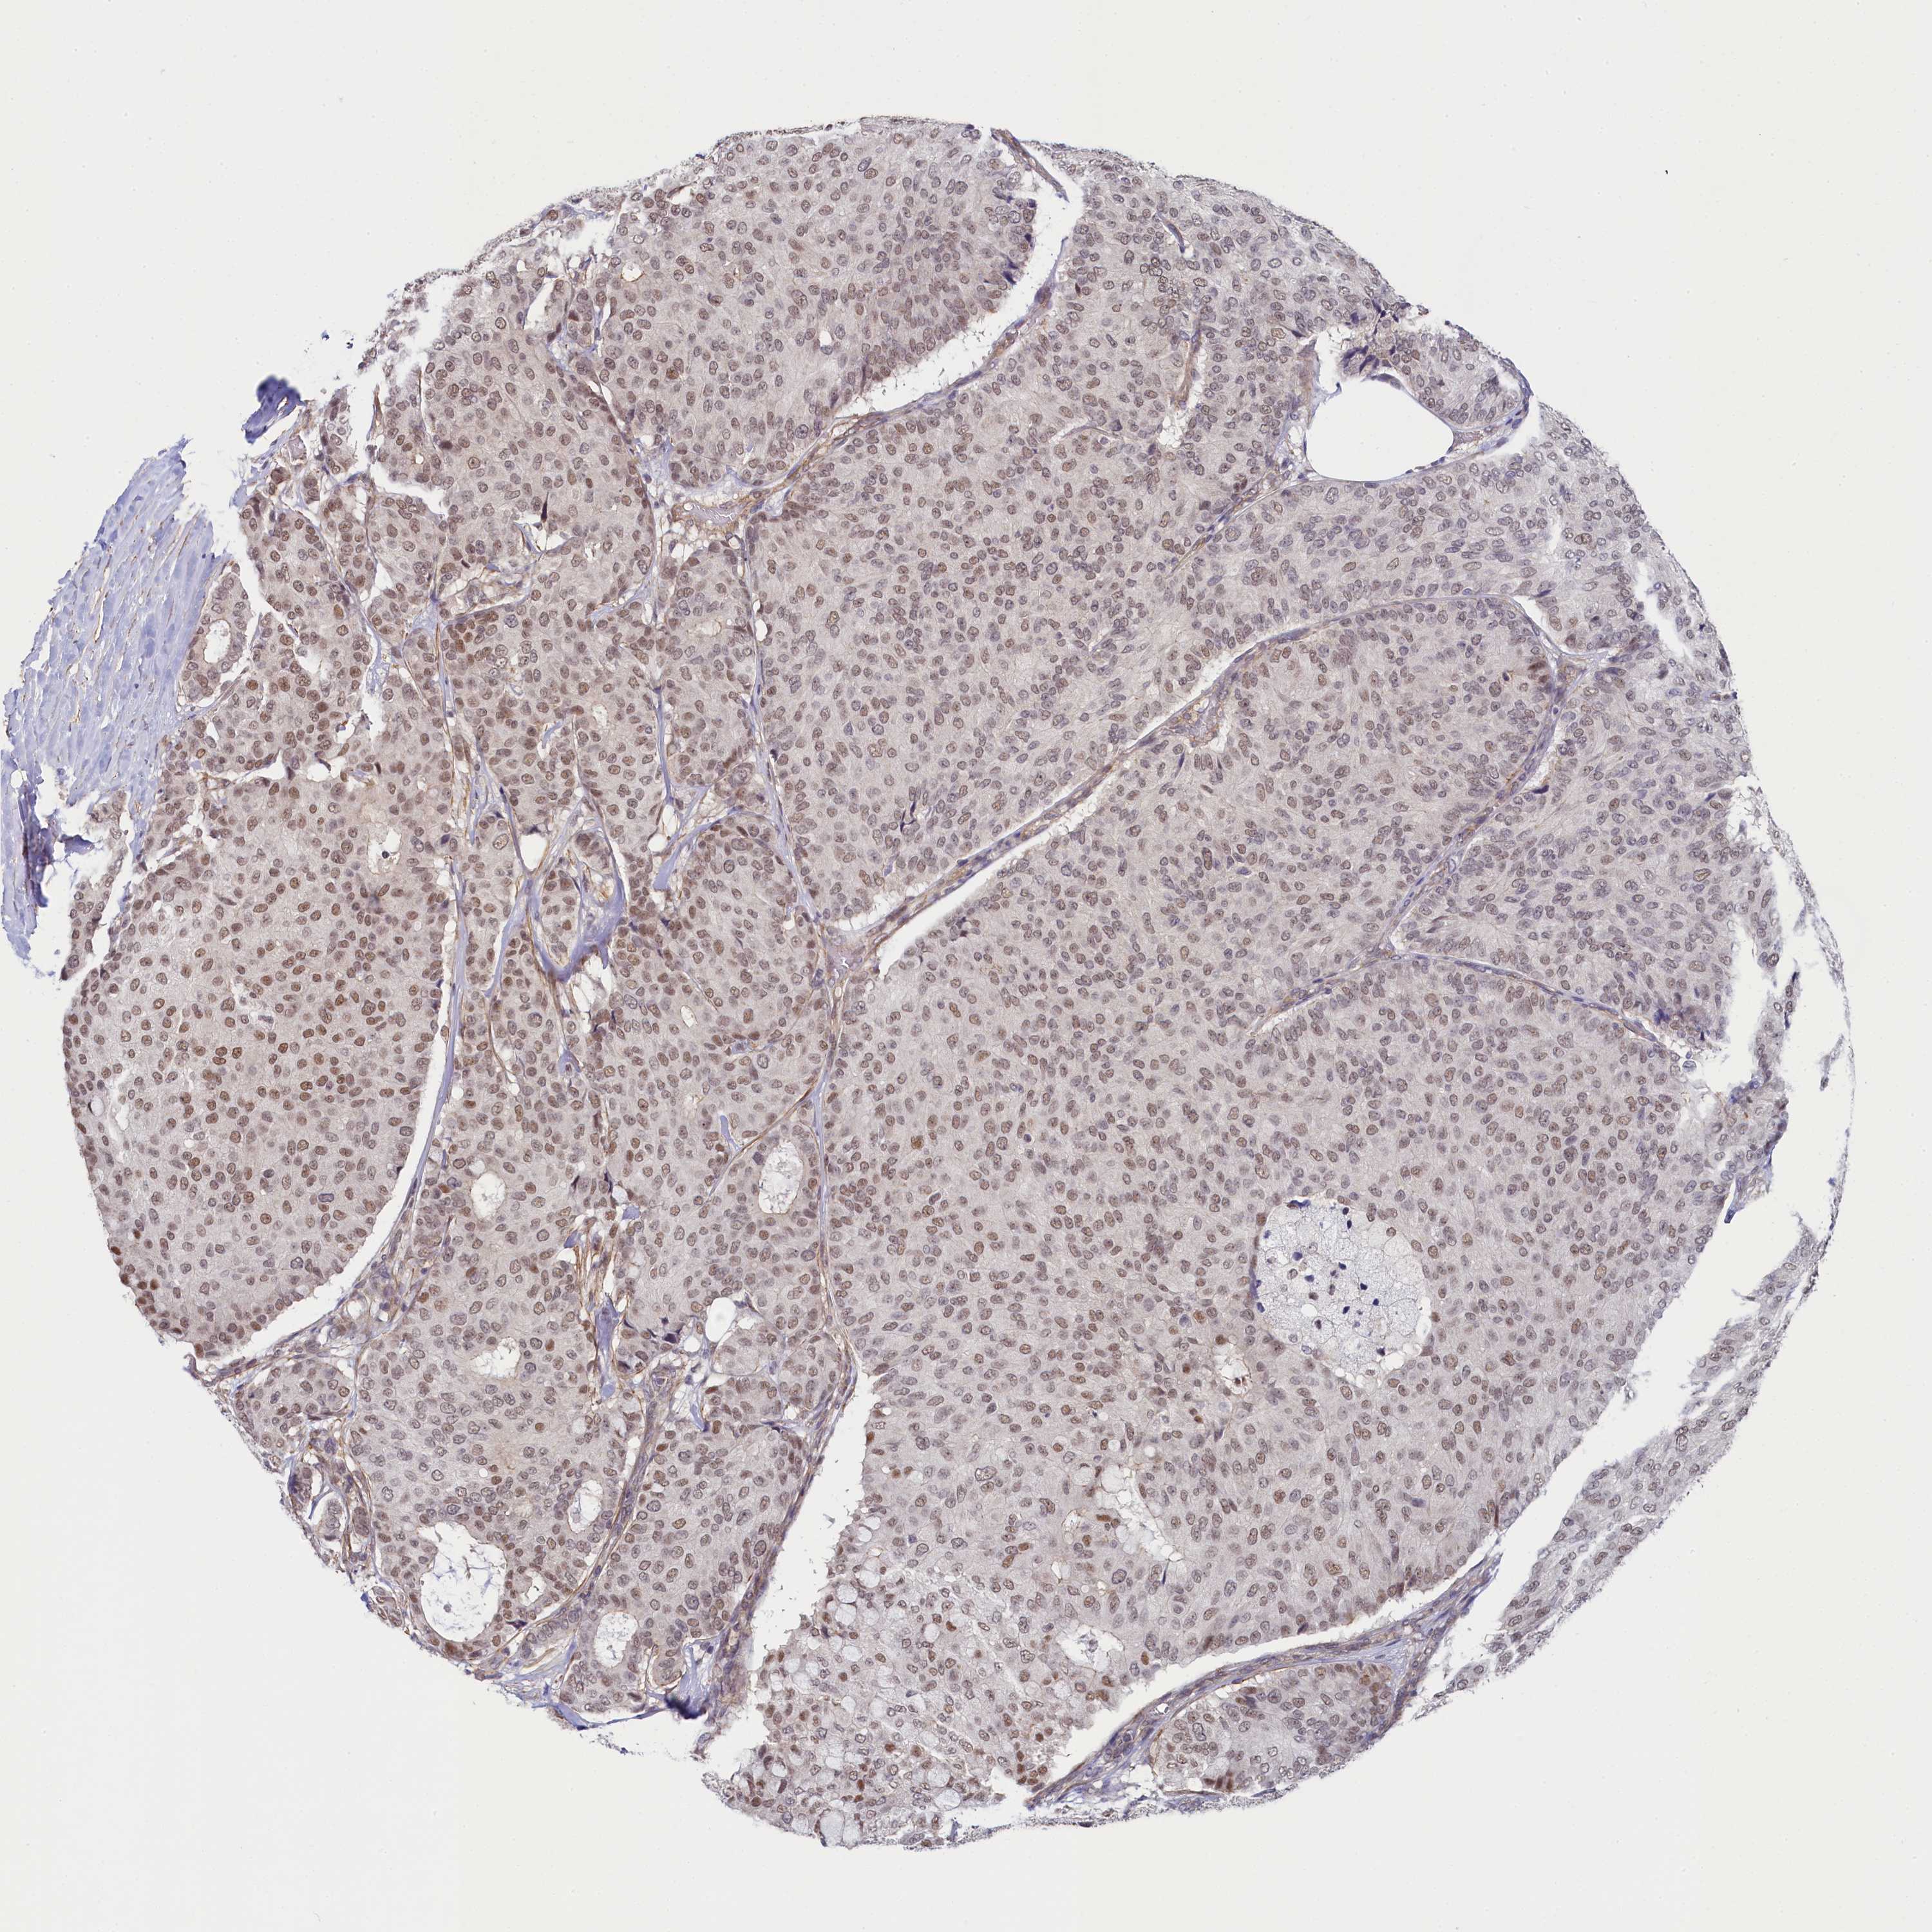

CANCER BREAST CANCER Show tissue menu

BRCA TCGA BRCA VALIDATION PROTEIN EXPRESSION